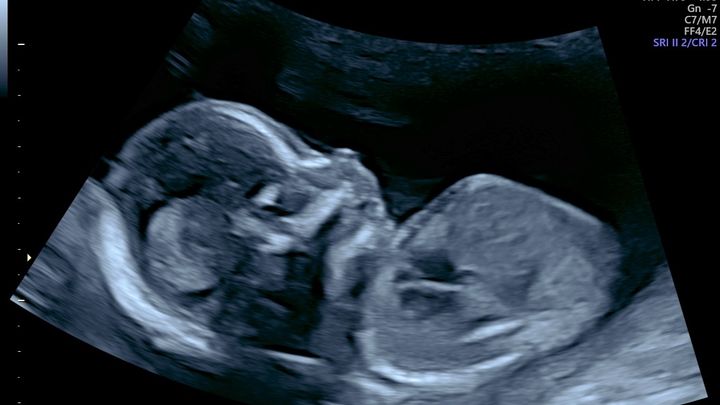

Our new baby Hector has been diagnosed with a heart condition called transposition of the great arteries as well as a heart abnormality which will require open heart surgery and other procedures to ensure his survival. While the odds are good for him the road is long, he will be required to have surgeries/procedures as soon as he is born and ongoing for months into his newborn life. Which will require lots of changes in our home, health and work schedules.